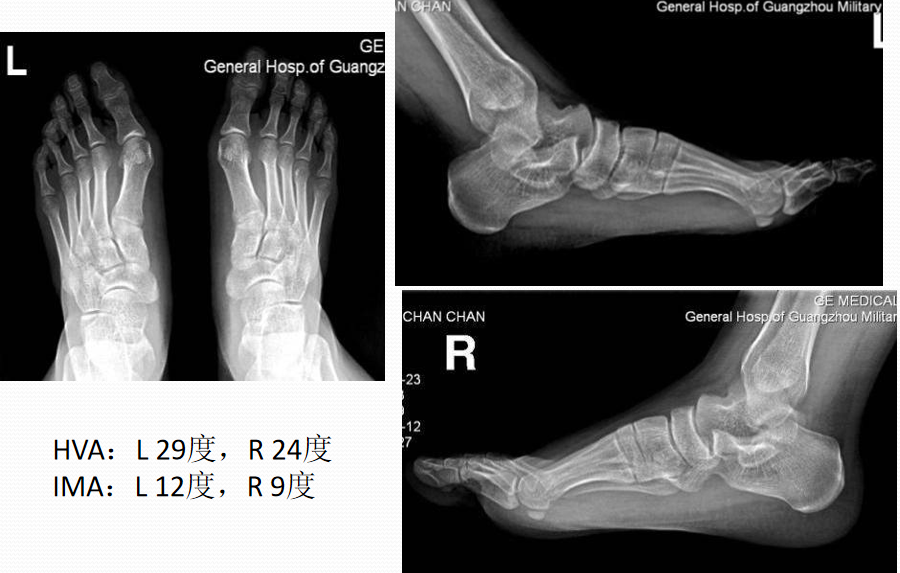

X线表现与测量

足的x线测量对于进一步了解拇外翻的病理及设计手术方案是非常重要。负重足的基本功能,很多足的畸形在负重状态下可以表现得更清楚。一些测量指标在负重和非负重状态下可以明显不同。足部各种x线测量一般都是在足负重位摄片下完成。手术前常规需要拍摄患足负重位、前后位和侧位,根据需要拍摄足的非负重位内旋斜位和籽骨轴位。

1:前后位观察和测量拇外翻角(HAA)  :拇趾跖骨中轴线与近节趾骨中轴线之夹角。正常为15°~20°

第1、2跖骨间夹角(IMA):  第1、2跖骨中轴线之夹角。正常为9 °拇外翻时此角通常大于正常。

拇外翻的分度与分类足踝外科学中Mann将拇外翻分为轻、中、重三度1.轻度  第1跖骨头内侧突出并有疼痛。HAA<30°,一部分畸形可由于趾骨间关节外翻引起,跖趾关节一般是适合的,IMA通常<13°,胫侧籽骨一般位于正常位置或有轻度移位,位于位置4。2.中度  拇趾外偏挤压第2趾,拇趾一般有旋前畸形,HAA30°~40°,IMA通常13°~ 16°,胫侧籽骨有明显脱位,位于位置6~7。3.重度  拇指外偏挤压第2趾形成骑跨趾,拇趾有中重度的旋前畸形,HAA>40°,IMA通常>16°,第2趾跖骨头下形成转移性跖骨痛。胫侧籽骨脱位于跖骨头腓侧缘外。

足踝外科学中Palladino按照拇外翻的发展过程将其进程分为4期I期  HAA正常,IMA正常,第1跖趾关节关系正常。Ⅱ期  HAA不正常,IMA正常,第1跖趾关节偏斜。Ⅲ期  HAA不正常,IMA不正常,第1跖趾关节偏斜。Ⅳ期  HAA不正常,IMA不正常,第1跖趾关节半脱位。(HAA:拇外翻角 ,IMA:第1、2跖骨间夹角)

典型病例例1:姚X,女,78Y。

Chevron+第二跖骨Weil